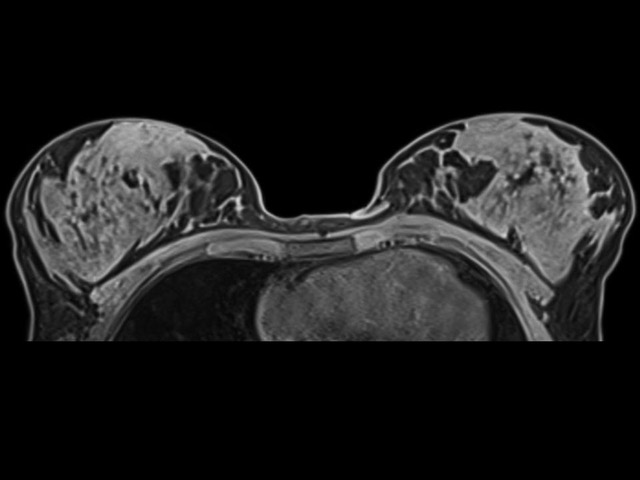

La RM Mammaria eseguita con il sistema Siemens Magnetom Vida 3T rappresenta l’eccellenza diagnostica attuale, combinando un’elevata intensità di campo (3 Tesla) con tecnologie basate sull’intelligenza artificiale per lo studio del seno.

• Alta Risoluzione Spaziale e Temporale: Grazie al campo da 3T, è possibile identificare lesioni piccolissime e studiare con estrema rapidità la vascolarizzazione dei tessuti, fondamentale per distinguere tra formazioni benigne e maligne.

Risonanza Magnetica Mammaria 3Tesla Vida Siemens IA